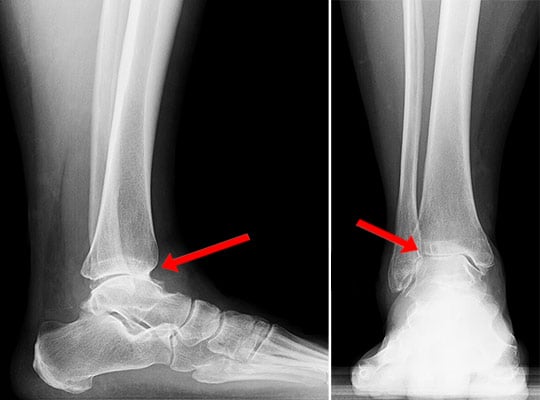

Lateral (side view) and anteroposterior (front view) X-rays showing end-stage arthritis with bone-on-bone contact in the ankle joint.